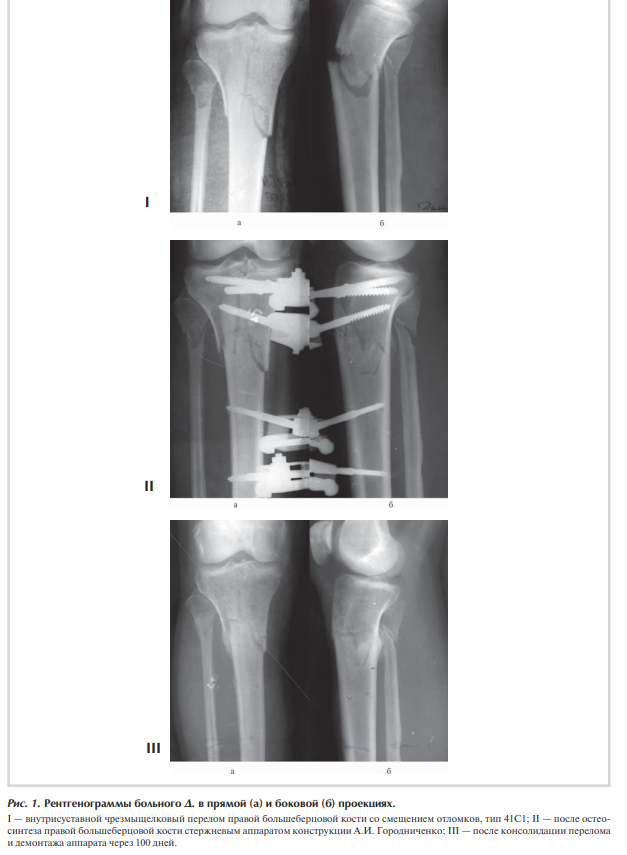

При осмотре отмечаются отек правого коленного сустава и верхней трети голени, болезненность при пальпации и положительный симптом баллотации правого надколенника. После клинико-рентгенологического обследования установлен диагноз: закрытый внутрисуставной чрезмежмыщелковый перелом правой большеберцовой кости со смещением отломков, тип 41С1 (рис. 1, I).

Сосудистых и неврологических расстройств в дистальных отделах правой нижней конечности не выявлено. При поступлении произведена анестезия места перелома, при пункции правого коленного сустава получено 60 мл крови с примесью жира, выполнена внешняя иммобилизация конечности гипсовой лонгетной повязкой. На следующий день под наркозом произведена операция: закрытая репозиция и чрескостный остеосинтез правой большеберцовой кости стержневым аппаратом конструкции А.И. Городниченко. Через разрезы кожи и мягких тканей по передневнутренней поверхности правой голени длиной до 8 мм введено три спонгиозных стержня в мыщелки большеберцовой кости и три кортикальных стержня в диафизарную часть. После фиксации проксимальных стержней в аппарате под контролем электроннооптического преобразователя произведена закрытая репозиция с помощью съемных рукояток с последующей стабилизацией дистальных стержней (рис. 1, II). Кожа вокруг стержней ушита одиночными швами.

Послеоперационное течение без осложнений, проводили регулярные перевязки с обработкой кожи вокруг стержней растворами антисептиков и сменой асептических повязок. Швы вокруг стержней сняты через 12 дней после операции, и пациент выписан на амбулаторное лечение с рекомендациями по дальнейшему восстановительному лечению. После консолидации перелома через 100 дней произведен демонтаж аппарата (рис. 1, III).